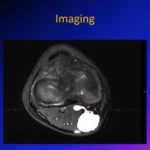

- Magnetic resonance imaging typically shows:

- A cystic structure within the anterior cruciate ligament

- A fluid-filled lesion with high signal intensity on T2-weighted images

- Magnetic resonance imaging can confirm the cyst and identify underlying intra-articular abnormalities.